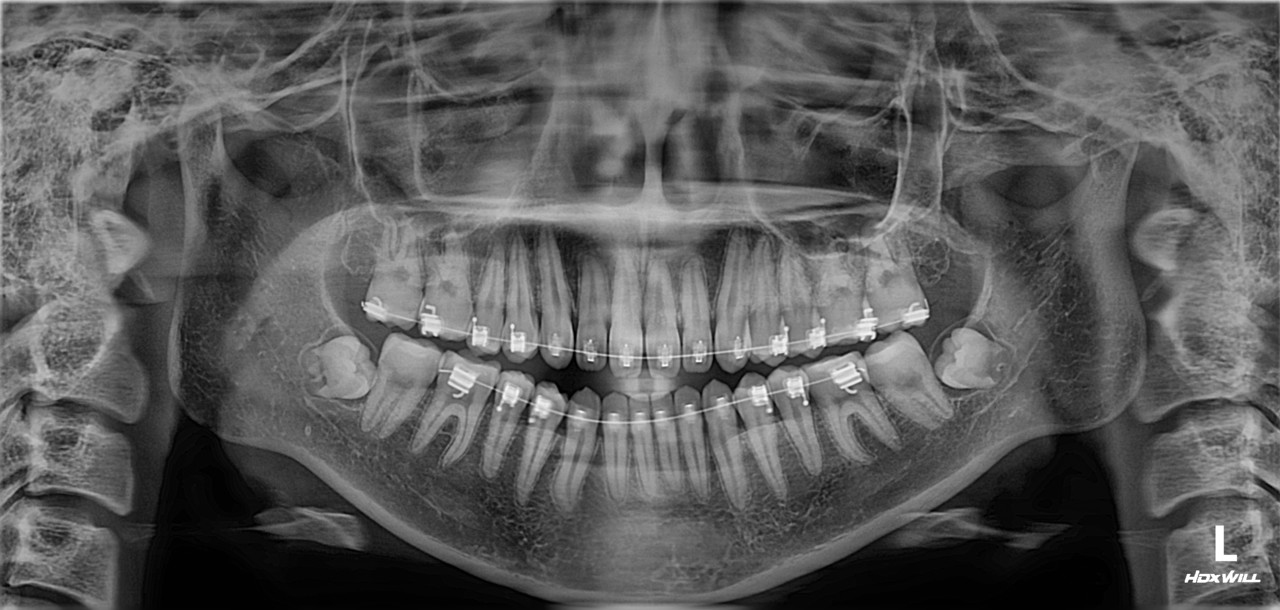

확장 개원 후, 첫 번째 사랑니 환자입니다. 잇몸 밖으로 보이지도 않고, 절개를 해도 뼈만 보이고 사랑니는 보이지를 않습니다. 이 정도면 사랑니 중에서도 난도가 높은 편입니다. 발치하는 데 얼마나 걸릴까요? 빨리 뽑는 것보다 잘 뽑는 게 중요하지만, 역설적으로 잘하는 의사는 빨리 뽑습니다. 그리고 약물 처방 외에도 주사 처방을 통해 붓기를 조절해 드립니다.

확장 개원 후, 첫 번째 사랑니 환자입니다. 잇몸 밖으로 보이지도 않고, 절개를 해도 뼈만 보이고 사랑니는 보이지를 않습니다.

이 정도면 사랑니 중에서도 난도가 높은 편입니다. 발치하는 데 얼마나 걸릴까요?